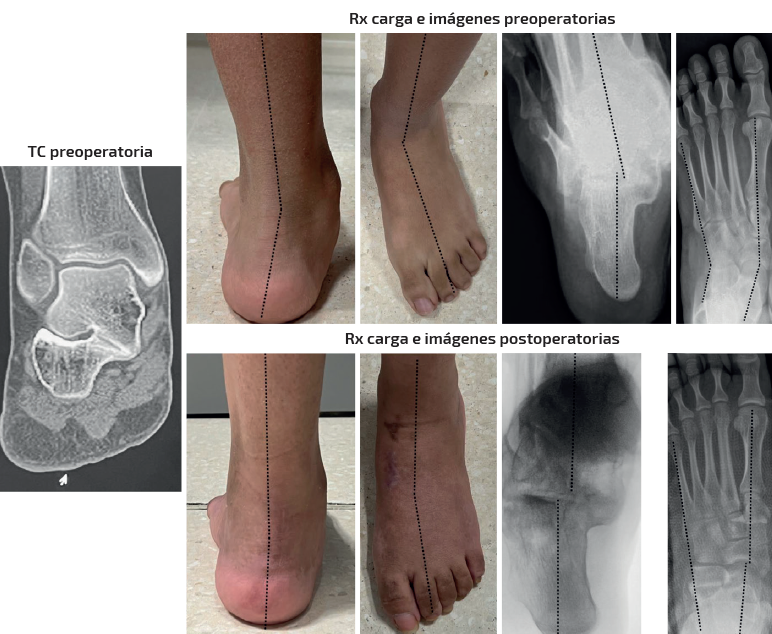

Caso 3 (Figura 6)

Se trata de una paciente mujer de 15 años. Afecta de coalición talocalcánea fibrocartilaginosa con deformidad en plano, valgo y abducto con subtalar rígida. Dolor medial y en sinus tarsi. Tipo IB de Myerson. Tratamiento: doble osteotomía (alargamiento de la columna externa + deslizamiento medial) en el calcáneo y osteotomía pronadora según Cotton + alargamiento del tríceps sural de tipo Strayer. Aloinjerto liofilizado de cresta. Seguimiento: 1,5 años. Mejoría de la alineación clínica y del dolor preoperatorio. Obsérvese cómo en este caso el astrágalo mantiene su flexión plantar en la radiografía lateral pero se ha corregido el abducto y el valgo clínicamente y en la radiografía dorsoplantar. También ha mejorado la altura del arco clínica y en la radiografía anteroposterior (AP) de tobillo (aumento de la altura de la interlínea del tobillo comparativa entre ambos tobillos pre- y postoperatoriamente).